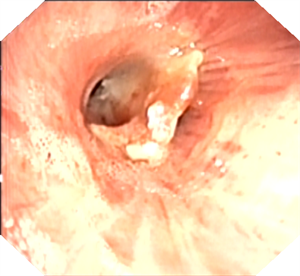

此时,消化内科吴主任直接接过 “接力棒”。在疼痛科主任朱华忠无痛麻醉监护及内镜护理人员配合下,成功取出异物——手表表带的生耳针。这一异物在支气管镜诊疗前,从患者支气管内咳出后又被吞入胃中。当异物被成功取出的那一刻,在场所有医务人员悬着的心终于放下。虽然当时已至凌晨一点多,但大家毫无疲惫之感,心中唯有成功救治患者后的喜悦。